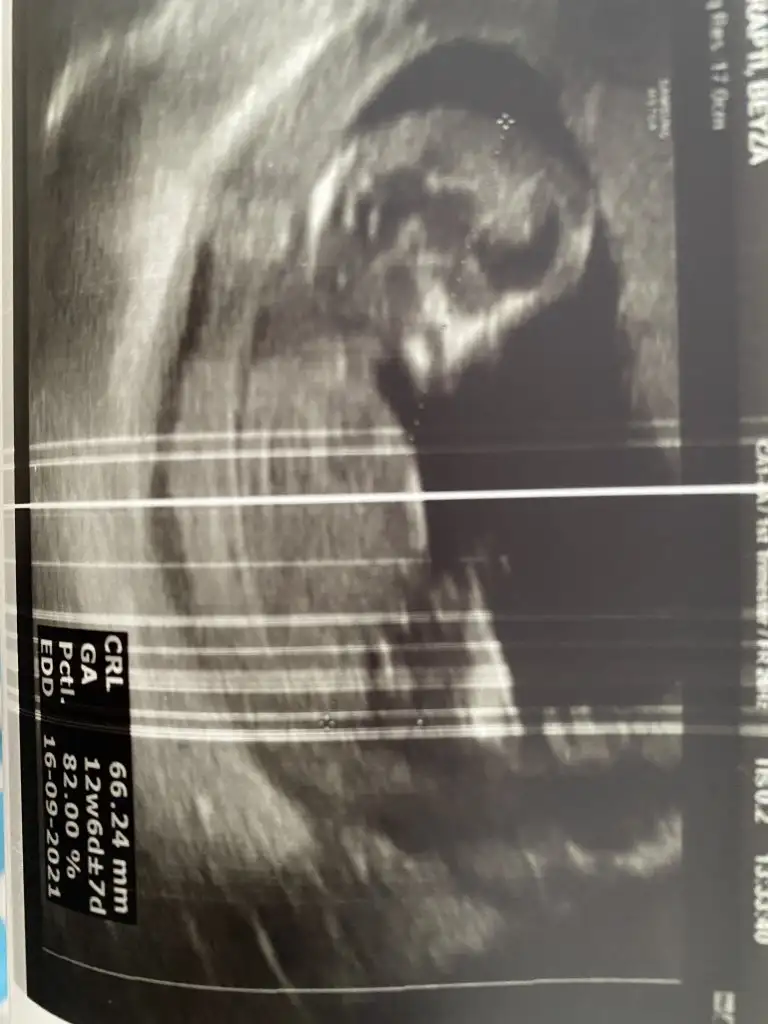

12+6. Tahmin eder misiniz lütfen 🌸